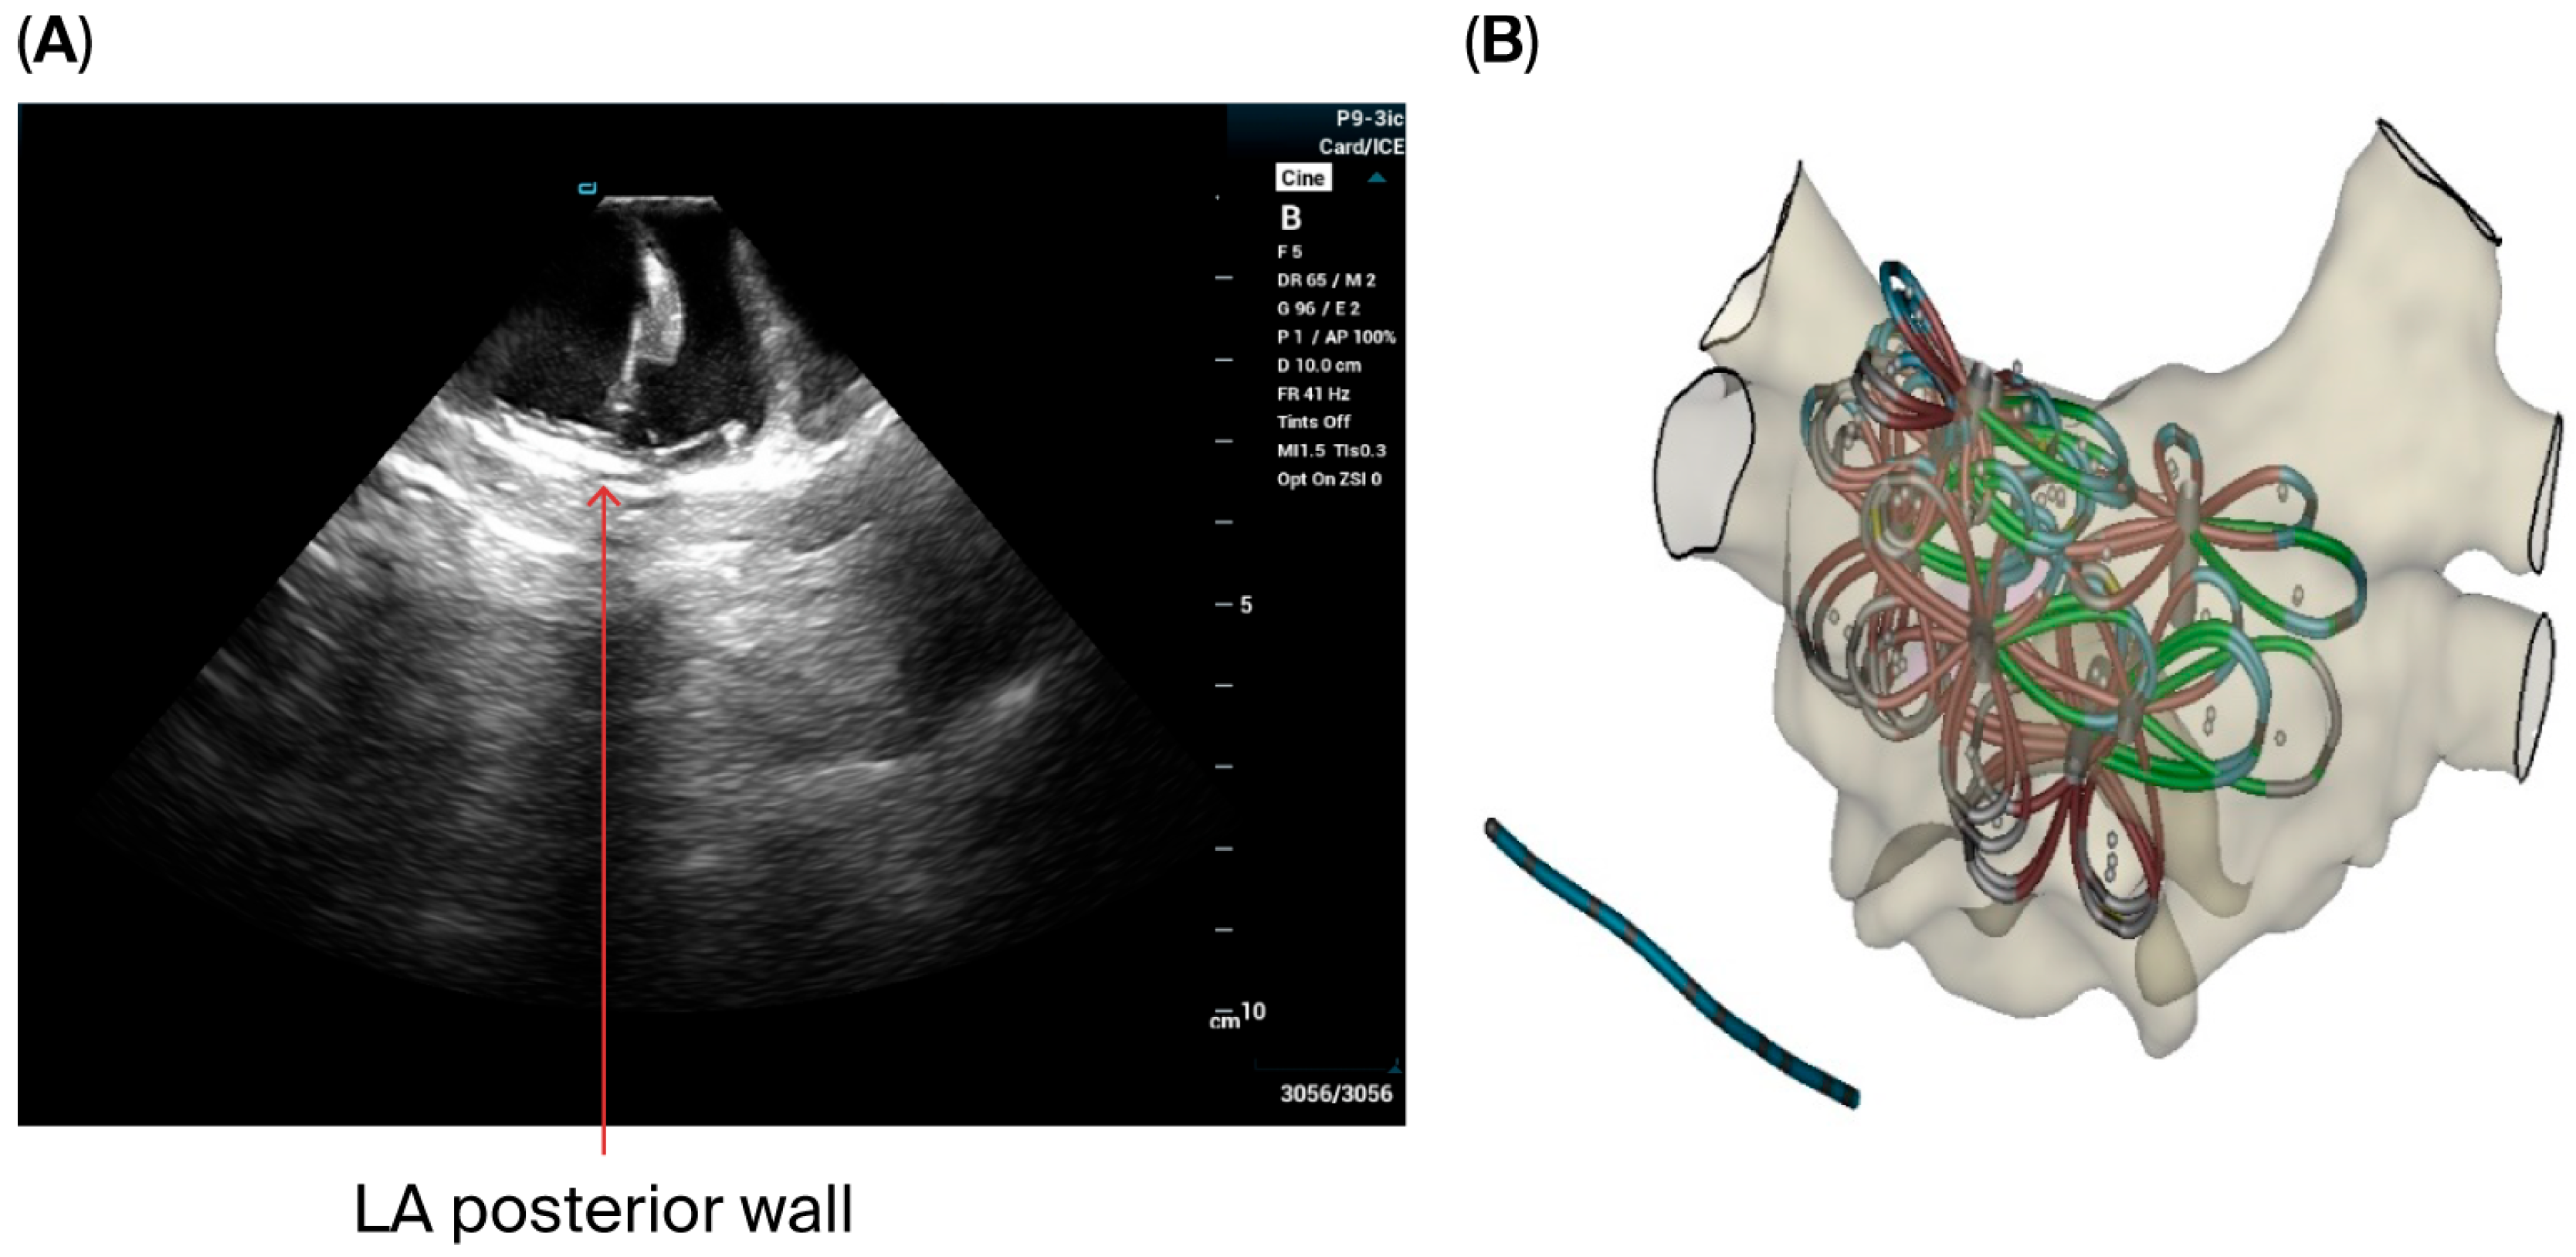

- The VersaCross sheath was exchanged for the Faradrive sheath and dilatator. After predilatation of transseptal puncture, the Faradrive sheath was retracted, and the ICE catheter was advanced along the VersaCross wire to the left atrium (Figure 1A–D). Then, the Faradrive sheath was moved back to the LA, and the dilator and Versacross wire were removed, with the ICE catheter and PFA sheath placed in the LA via a single transseptal puncture.

- ICE images of the LA, including the LAA, were obtained from all patients to exclude LAA thrombus (Figure 1E).

- A circular mapping catheter (CMC) or high-density catheter (with repeated ablation) was advanced to the LA via the Faradrive sheath. Electroanatomic mapping of the LA, including detailed voltage assessment was performed. Then, over the J-tip wire, the Farawave pentaspline catheter was advanced to the LA via the Faradrive sheath. The 0.035-inch J-tip guidewire was attached to the EnSite mapping system’s pin box via a DuoMode extension cable (Boston Scientific, Marlborough, MA, USA) for additional visualization in LA and pulmonary veins. ICE catheter imaging was used to ensure appropriate catheter positioning and catheter–tissue contact with each PV and LAPW PFA lesion delivered. Prior to ablation, 0.2 mg of intravenous glycopyrrolate was administered to all patients to avoid vagal reactions during PVI.

- LAPW isolation was achieved with overlapping lesions placed in the flower configuration, with 2 application per site. With the J-tip wire in the left PV serving as a ‘hook’, rotating the catheter clockwise in the flower configuration allowed ablation of the posterior wall near the left veins; similarly, with the J-tip wire in the right pulmonary veins, rotating the catheter counterclockwise allowed appropriate contact for the posterior wall isolation near right veins. Remaining mid-posterior wall was ablated with overlying lesions in the flower configuration. ICE was used with each ablation application to ensure optimal contact.